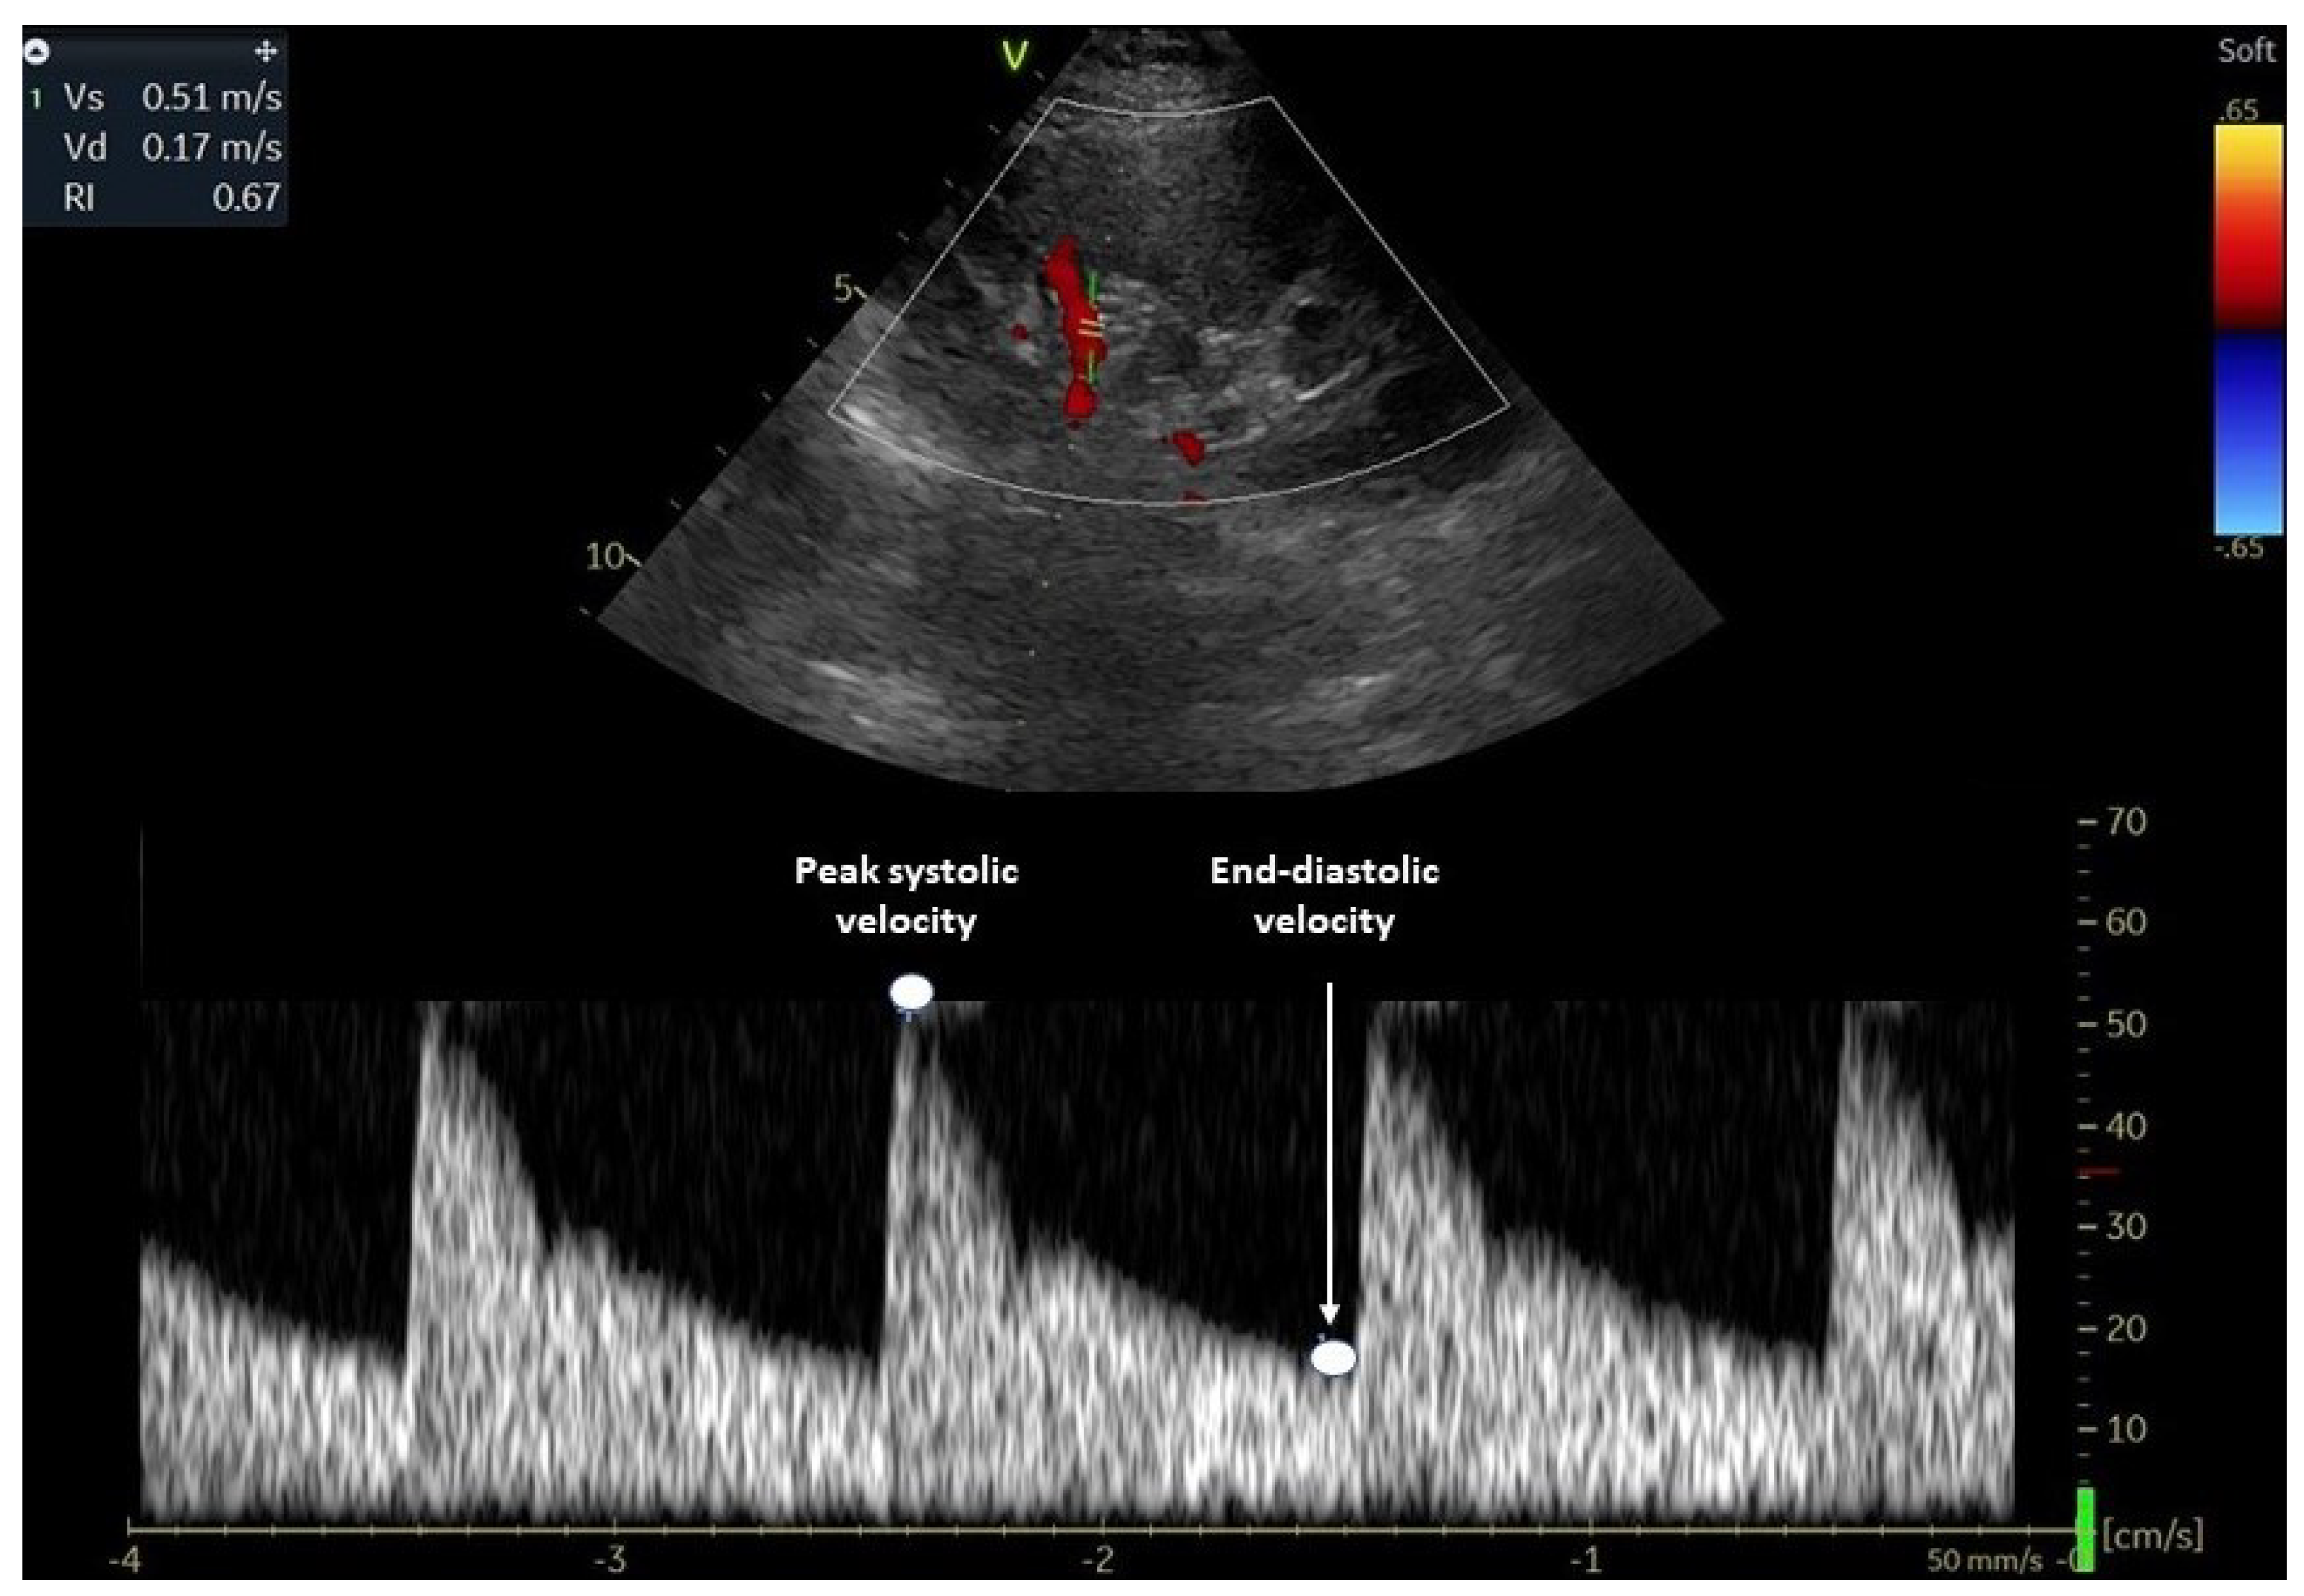

2. Evaluation of Renal Resistive Index